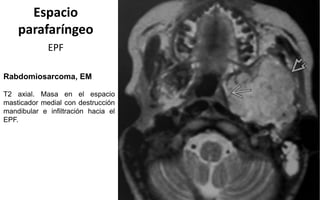

Espacio

parafaríngeo

EPF

Rabdomiosarcoma, EM

T2 axial. Masa en el espacio

masticador medial con destrucción

mandibular e infiltración hacia el

EPF.